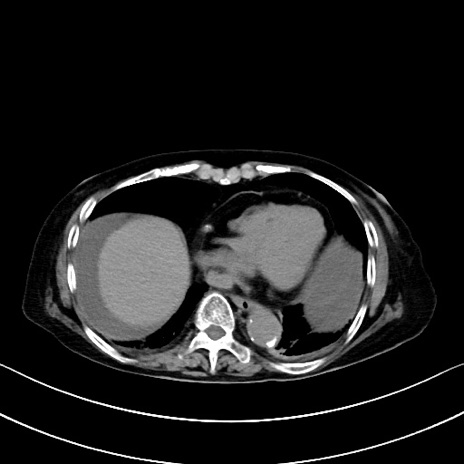

横断像

他院CT